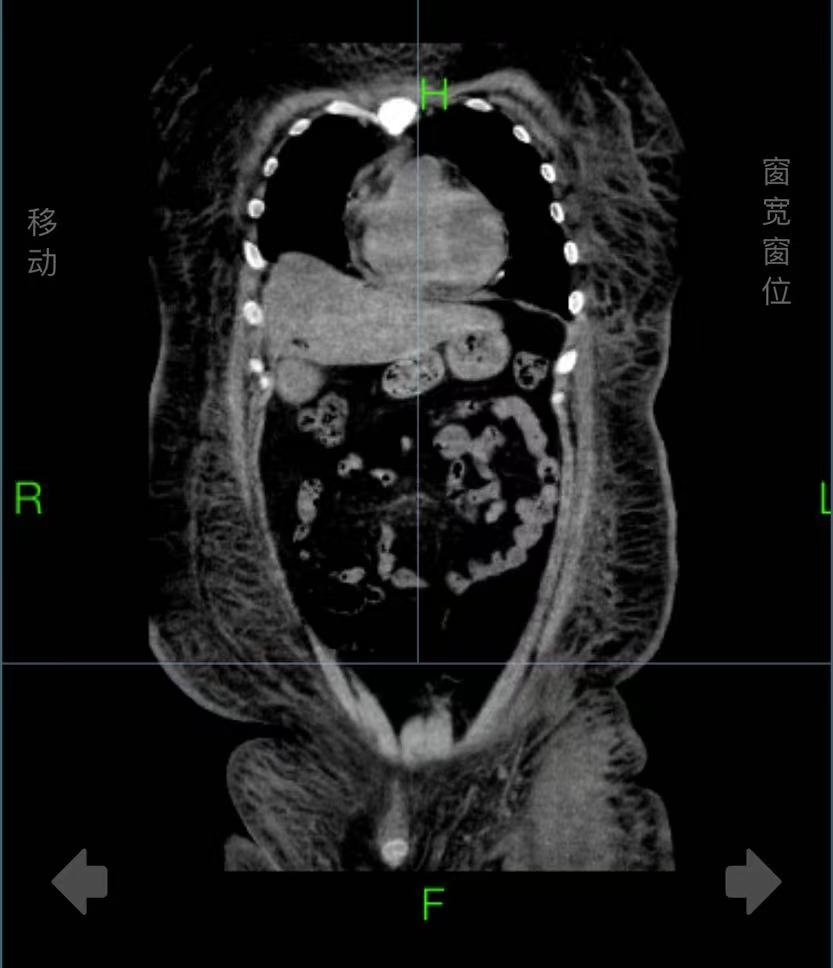

入院时,戴先生面色苍白,血氧饱和度低,全身高度水肿,情况十分危急。急诊三部主任张兴文、副主任医师徐静、贾爱军和护士长徐芙蓉等组成的医护团队立即组织抢救,给予患者利尿强心、补充白蛋白,无创呼吸机支持治疗等抢救措施。因患者体重太重,且高度浮肿,不仅输液抽血成问题,需要在超声引导下穿刺置管,连翻身检查都需要五六人齐上阵才能完成。经检查发现,患者心、肺功能衰竭,严重贫血、双侧胸腔积液、脂肪肝、皮下水肿,被诊断为重度营养不良、重度低蛋白血症、慢性营养不良性贫血和贫血性心脏病。住院期间,除了输血、利尿、强心和补充白蛋白等治疗外,医院营养体重管理专家蔡华教授还为戴先生制定了个性化的营养计划。通过10余天治疗,目前戴先生终于康复出院,且成功“瘦身”30斤。